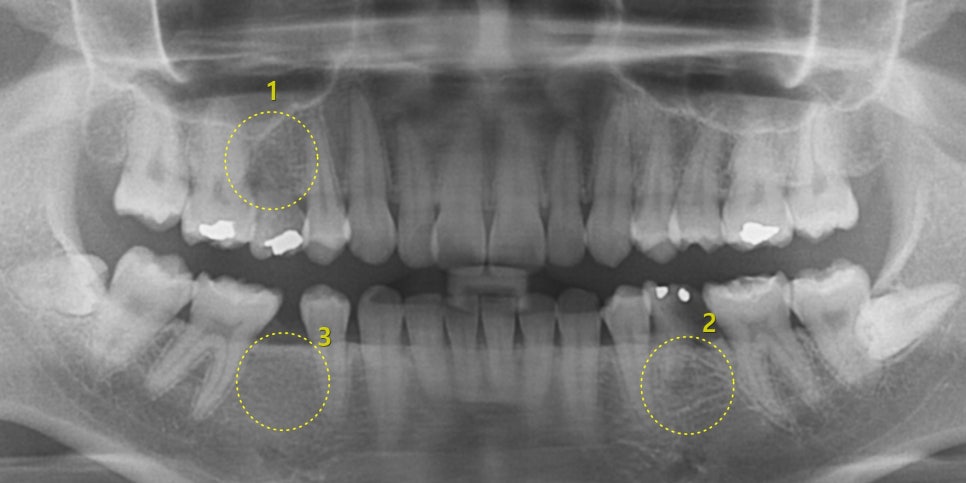

사진에서 1, 2번을 보시면

다른 치아(영구치)와 달리 뿌리가 매우 얕고 잘 보이지 않습니다.

3번은 6번 영구치가 있어야 할 곳인데 비어 있습니다.

1, 2번자리의 유치는 발치하고,

1,2,3번 자리 3군데에 임플란트를 식립하였습니다.(아래 사진)